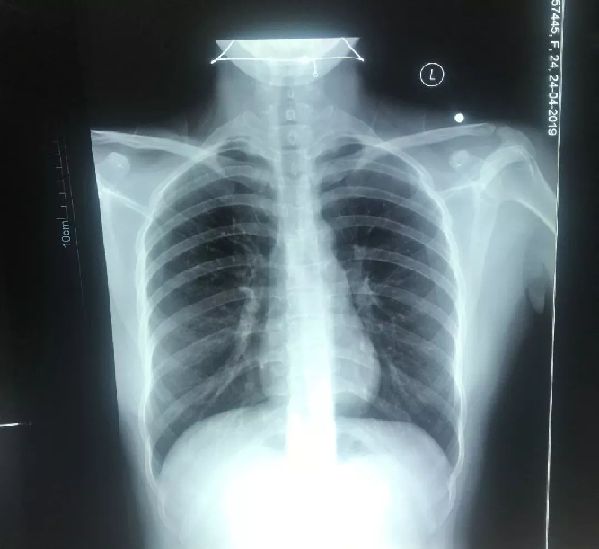

同时,在查体中发现,目前王某全身至少有7处弹片伤,主要集中在四肢、臀部和背部。其中在膝关节腘窝位置有集中弹片伤,弹片周围有丰富的血管和神经,这对于后期手术来说是一个巨大的挑战。

自绘人体图,红色标注的是目前看到的伤口。

白点为部分弹片位置。